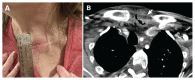

Figure 1:

(A) Cellulitis of the neck from colonic diverticulitis in a 55-year-old woman with previous reconstruction of esophageal atresia using a segment of colon. (B) A contrast-enhanced computed tomography scan showed findings typical of diverticulitis, including a fluid-filled false diverticulum (arrow), bowel wall thickening, subcutaneous fat stranding and edema.